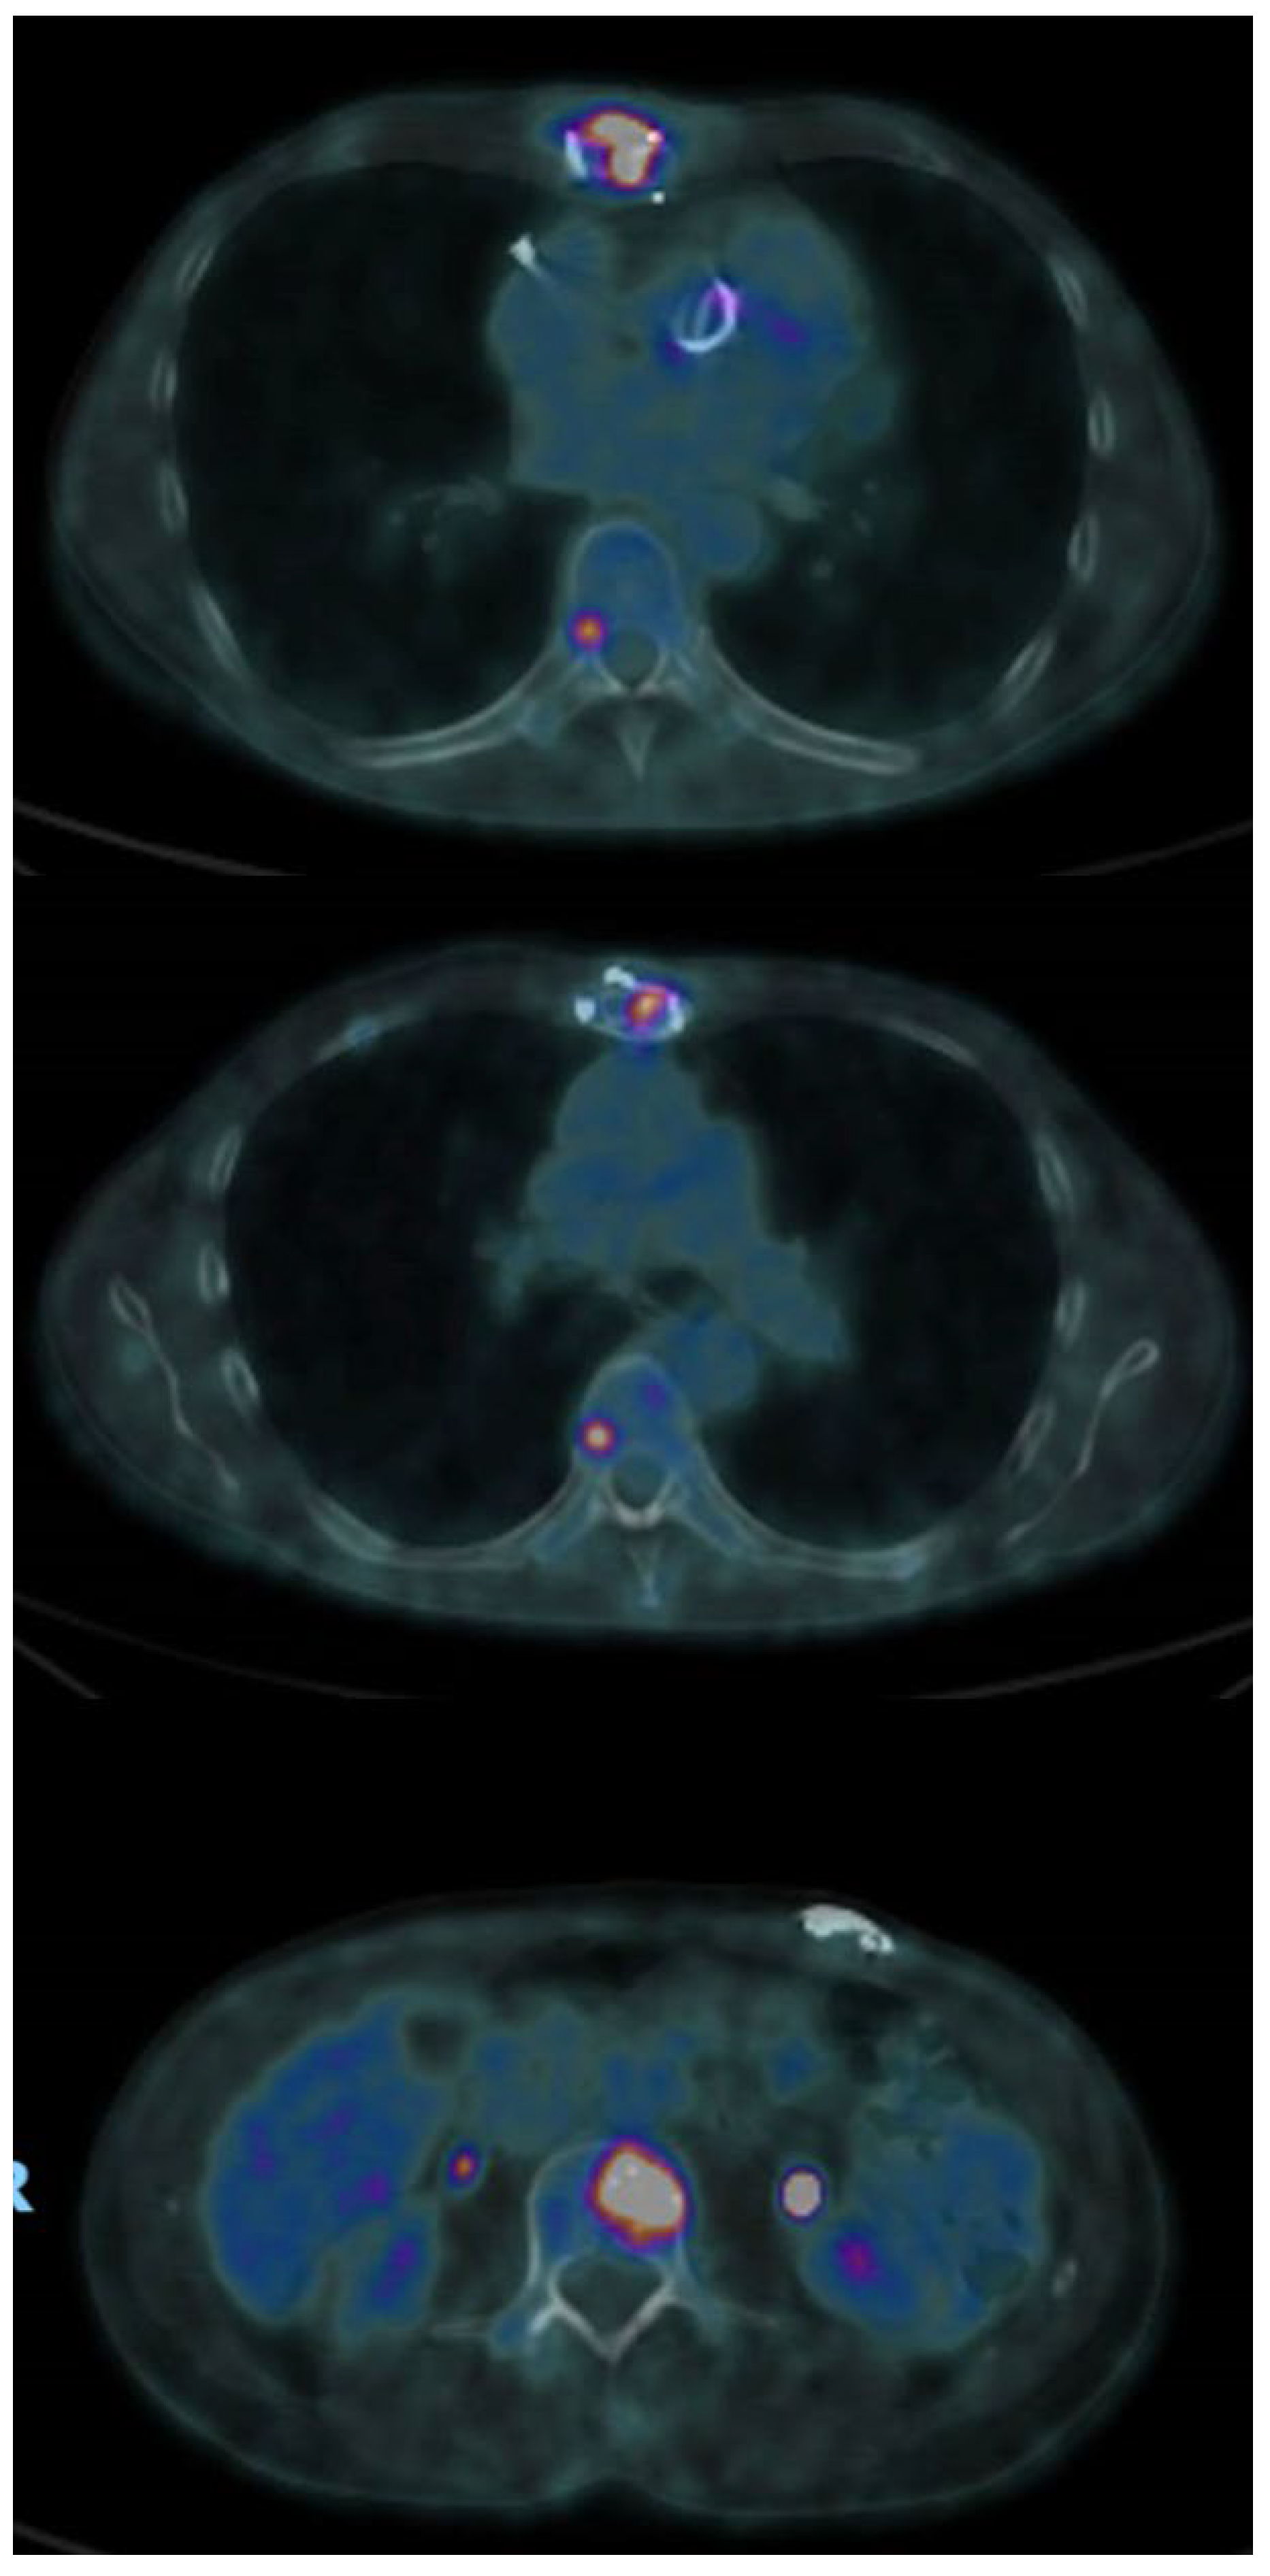

2. Case Report